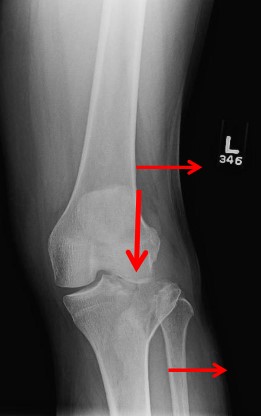

Переломи проксимального відділу гомілки становлять значну проблему сучасної травматології та ортопедії та складають близько 1,2% усіх переломів кісток. Ці пошкодження охоплюють переломи виростків великогомілкової кістки, переломи плато великогомілкової кістки та переломи головки малогомілкової кістки. Особливу увагу привертають внутрішньосуглобові переломи плато великогомілкової кістки, оскільки вони безпосередньо впливають на функцію колінного суглоба та можуть привести до тяжких віддалених наслідків.

Класифікація за Schatzker. Type I: Split fracture of the lateral plateau, Type II: Split depression fracture of the lateral plateau, Type III: Pure depression fracture of the lateral plateau, Type IV: Medial plateau (possible fracture / dislocation), Type V: Bicondylar plateau fracture, Type VI: Plateau fracture with metaphyseal / diaphyseal dissociation

Класифікація за AO/ASIF. Type A: Extraarticular fracture (41-A), Type B: Partial articular fracture (41-B), B1: Pure split, B2: Pure depression, B3: Split depression, Type C: Complete Articular fracture (41-C), C1: Simple articular, Simple metaphyseal, C2: Simple articular, Multi-fragmentary metaphyseal, C3: Multifragmentary articular

Клінічне обстеження. При первинному огляді виявляють біль, набряк, деформацію в ділянці колінного суглоба, обмеження рухів, гемартроз. Обов’язковим є оцінка стану м’яких тканин, перевірка периферичного кровообігу та неврологічного статусу кінцівки. Особливу увагу приділяють виключенню синдрому тривалого здавлювання та компартмент-синдрому.